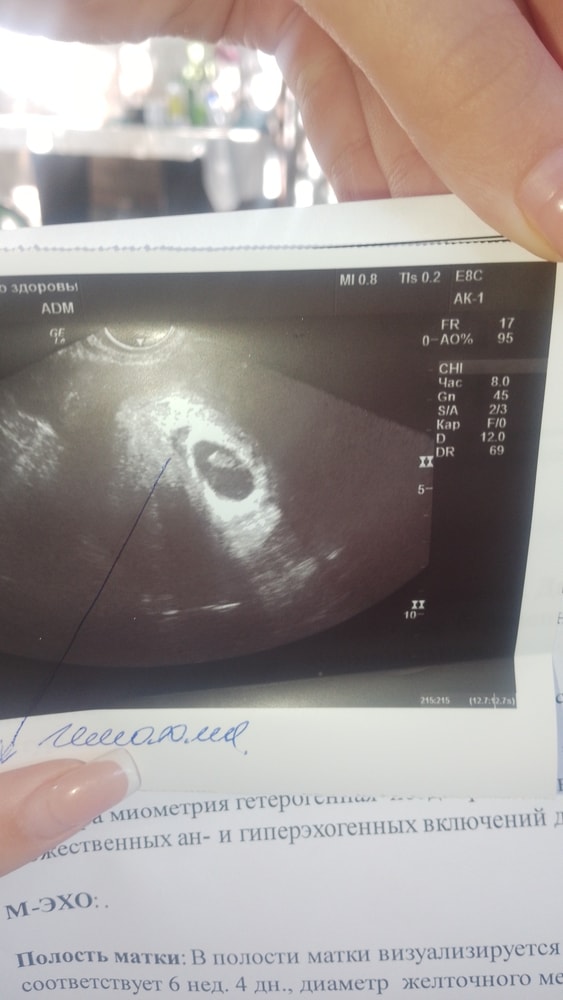

Гематома

Здравствуйте, подскажите пожалуйста может ли выходить эта гематома кусками и бурой кровью или это начавшийся выкидыш?